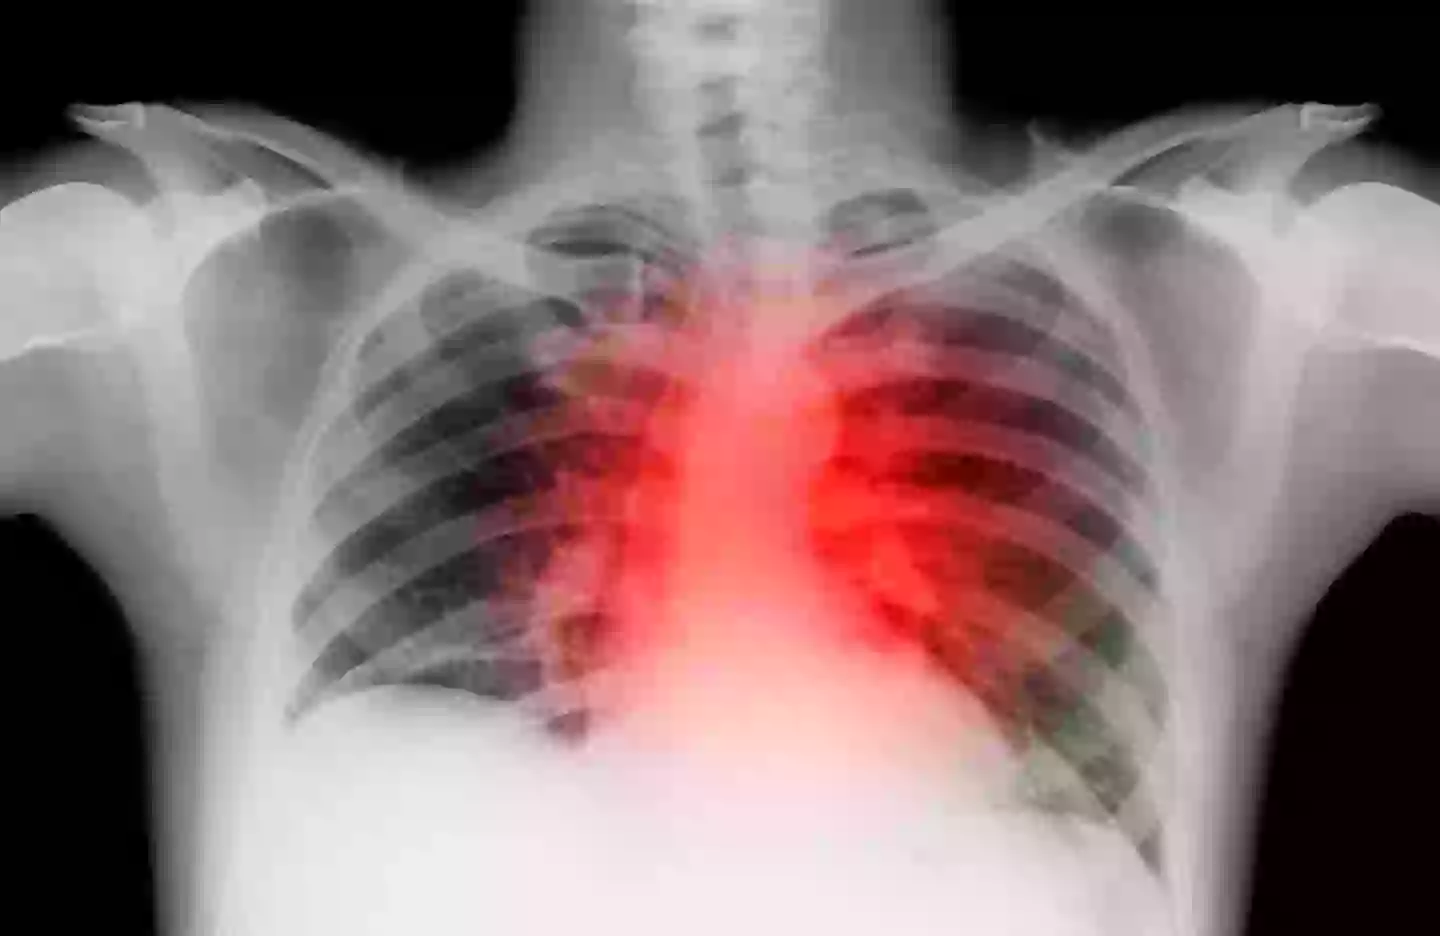

Over consuming protein, particularly animal protein, can increase your risk of heart disease (Getty Stock Image)

Instead people should be looking to consume ’20 to 30 grams’ of protein as part of a varied diet (Getty Stock Image)